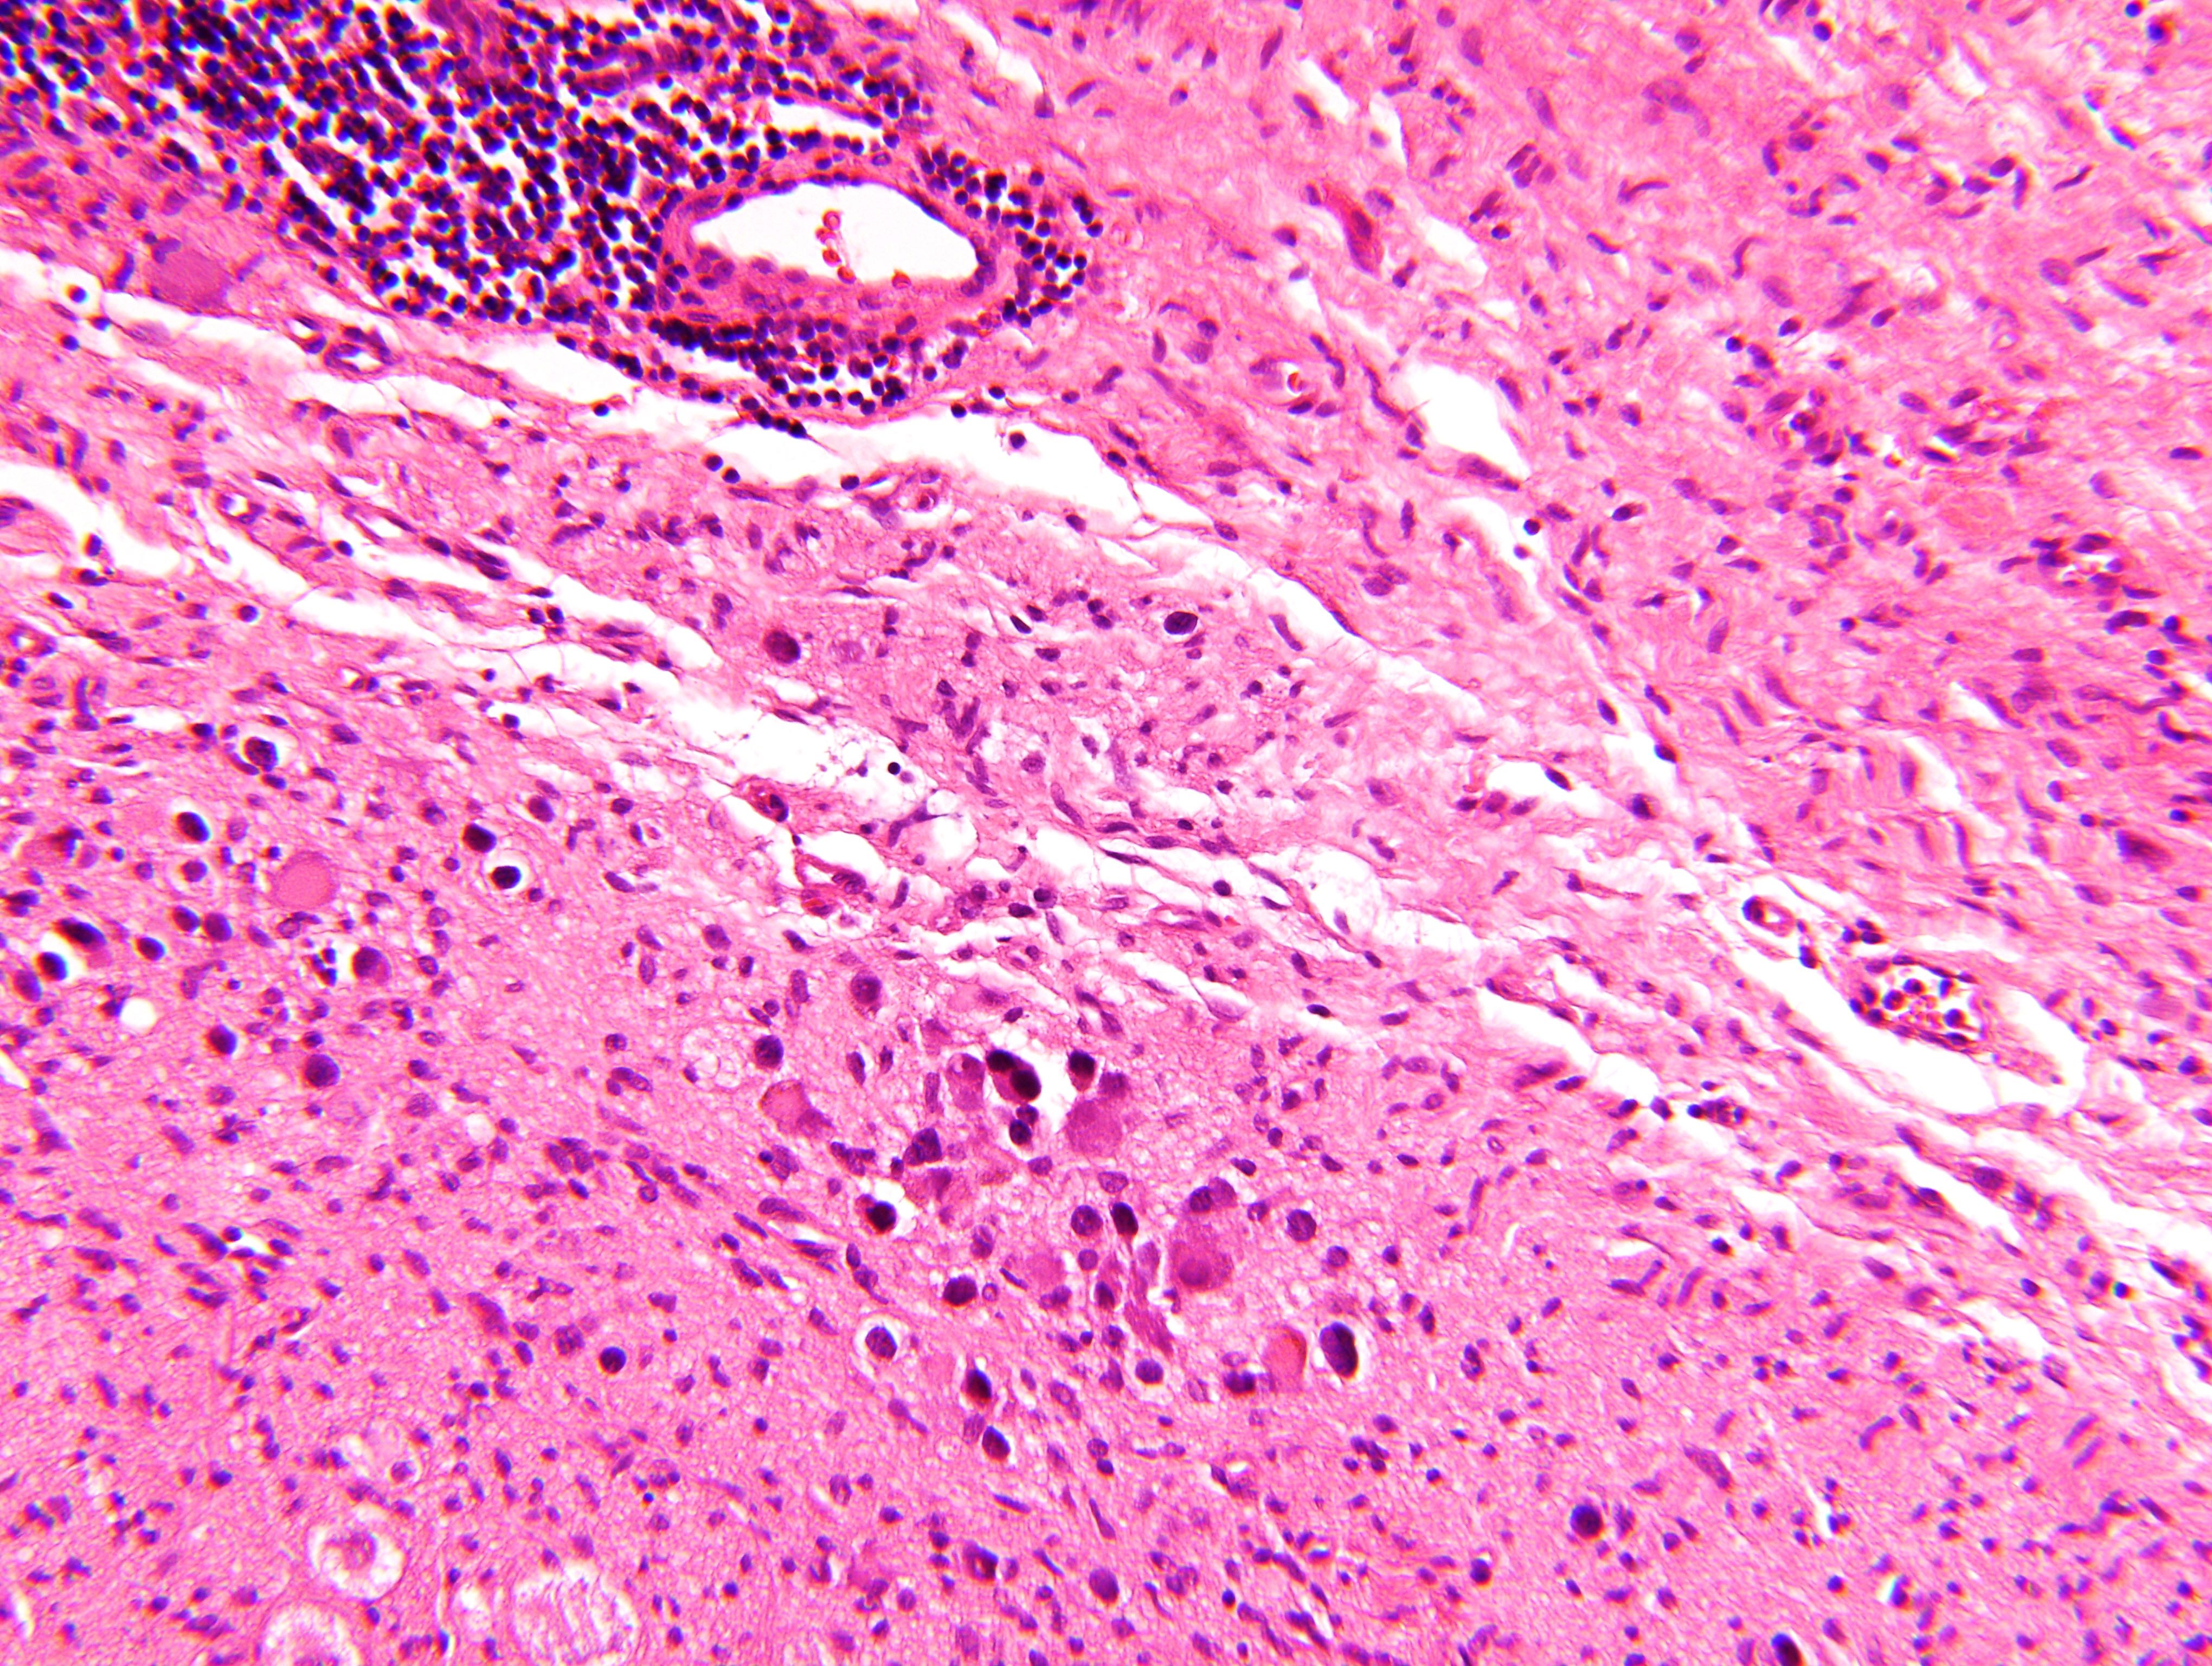

Microscopic (histologic) description

- Architecture: lobular, diffuse / solid, organoid

- Neuroblasts

- Homer Wright pseudorosettes = circular, ovoid, angular zones of pale staining neuritic cell processes surrounded by tumor cell nuclei; may rarely palisade

- Minimal cytoplasm, may have cytoplasmic tail

- Round to ovoid nuclei with stippled salt and pepper chromatin, inconspicuous nucleoli

- Ganglion cells

- Abundant granular eosinophilic cytoplasm (Nissl substance = rough endoplasmic reticulum)

- Distinct cell borders

- Nuclear enlargement, eccentric nuclei, prominent nucleoli

- May see neuromelanin pigment (brown, finely granular; rarely present), cystic degeneration, hemorrhage, dystrophic calcification

Microscopic (histologic) images

Contributed by Carmen Perrino, M.D. and Debra L. Zynger, M.D.

Intermixed type

Nodular type